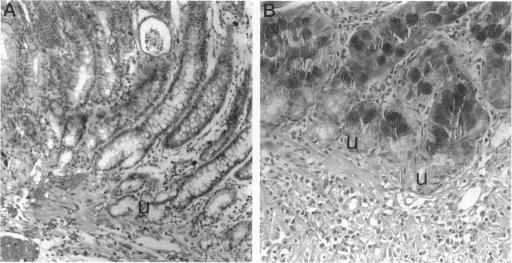

We have studied the histological changes observed in the mucosa of 10 rats in the region of a esophagojejunostomy to evaluate it as a model for the ulcer-associated cell lineage (UACL). In man, the UACL has a distinctive morphology, proliferative organization, and pattern of trefoil peptide localization. We have therefore examined these aspects aided by immunohistochemistry and in situ hybridization to the trefoil peptides TFF1, TFF2, and TFF3. Only TFF2 was studied by immunohistochemistry, whereas the mRNAs for all three peptides were examined by in situ hybridization using 35S-labeled riboprobes. The marker MIB-1 to the Ki67 proliferation-related antigen was used to examine the proliferative organization of UACL-like changes. In all cases, columnar epithelialization of the distal esophagus was seen, and in all, glands with morphological and gene expression attributes of the UACL were identified. TFF3 mRNA localized patchily throughout the UACL, whereas TFF1 mRNA was found in the upper portions of the lineage and TFF2 mRNA and its product in the acini. These lineages showed virtually no intrinsic proliferative activity. These appearances are similar to those seen in early human UACL, and we therefore propose this that this represents the first published animal model of this lineage.

我们研究了10只大鼠食管空肠吻合术区域黏膜的组织学变化,以评估其作为溃疡相关细胞谱系(UACL)模型的可行性。在人类中,UACL具有独特的形态、增殖组织和三叶肽定位模式。因此,我们借助免疫组织化学和针对三叶肽TFF1、TFF2和TFF3的原位杂交技术对这些方面进行了研究。免疫组织化学仅研究了TFF2,而使用35S标记的核糖探针通过原位杂交检测了所有三种肽的mRNA。使用针对Ki67增殖相关抗原的标记物MIB-1来检查UACL样变化的增殖组织。在所有病例中,均可见远端食管柱状上皮化生,并且均鉴定出具有UACL形态和基因表达特征的腺体。TFF3 mRNA在整个UACL中呈散在分布,而TFF1 mRNA见于该谱系的上部,TFF2 mRNA及其产物见于腺泡。这些谱系几乎没有内在增殖活性。这些表现与早期人类UACL所见相似,因此我们认为这是该谱系首个发表的动物模型。